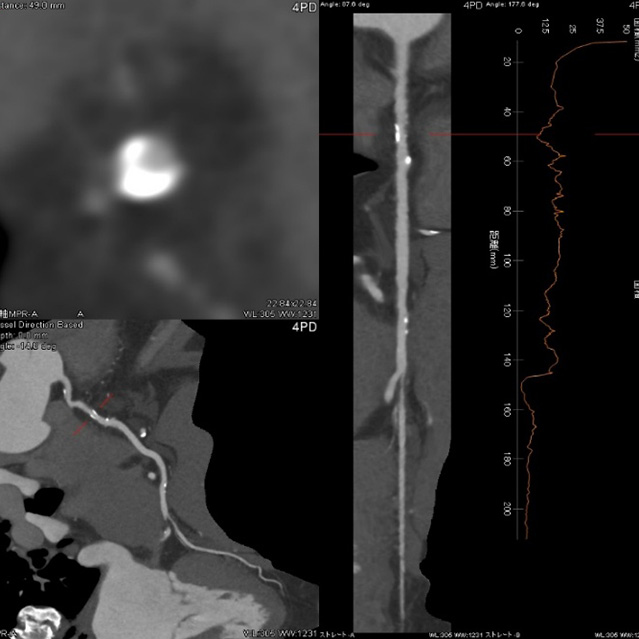

画像診断装置・放射線治療装置紹介

X線CT装置

64列 MDCT Aquilion CX (canon)

80列 MDCT Aquilion PRIME (canon)

80列 MDCT Aquilion PRIME SP(canon)

大きなトンネルの中に体を入れて、X線をあてて体の輪切りの写真を撮ります。CT検査には、単純CT検査と、造影剤を注射して撮影する造影CT検査があります。